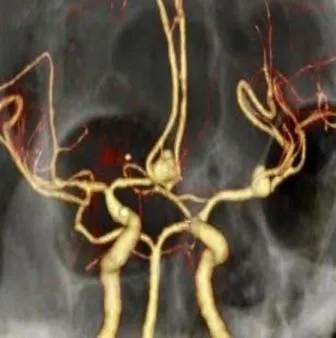

近日凌晨,峨眉山市人民医院急诊科接到内蒙古游客求救电话,55岁的鞠先生来峨眉旅游,突发剧烈头痛、呕吐,救护车随即出发,凌晨2点25分将患者接回医院,急诊头颅CT显示:大量蛛网膜下腔出血。神经外科副主任医师杨志敏立即前往急诊科会诊,根据多年丰富的临床经验,杨志敏医生判断患者为颅内动脉瘤破裂导致的蛛网膜下腔出血,急诊CTA影像结果提示:患者颅内前交通动脉及左侧大脑中动脉分叉处分别有9.5*7.7mm和7.4*5.6mm两个动脉瘤,随时可能再次破裂。